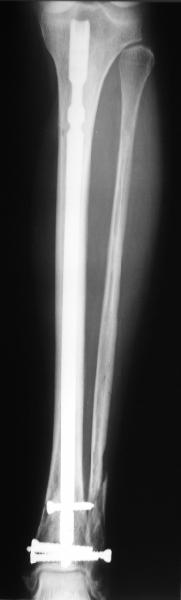

A typical case is attached, also an image with intra-op reduction obtained by a small wire distractor, in the moment of insertion a Poller wire in AP direction. Fixation by a SIGN nail. Despite the fibula was not fixed healing was obtained with the unchanged alignment.

Very interesting application, but is the final position in a little distal varus with some fibula

distraction? Would that have been eliminated by fibula plating?

At least both the ankle mortise and tibial alignment look acceptable, don't they?

I am just trying to illustrate that prevention of 1)tibial valgus and 2)loss of reduction can be provided without fibular plating. Small changes of conventional nailing techniques allow to maintain reduction of the tibia reliably without adjunctive fibular stabilization.